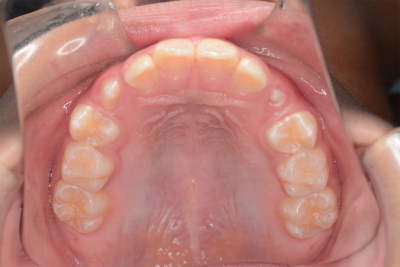

小学5年生